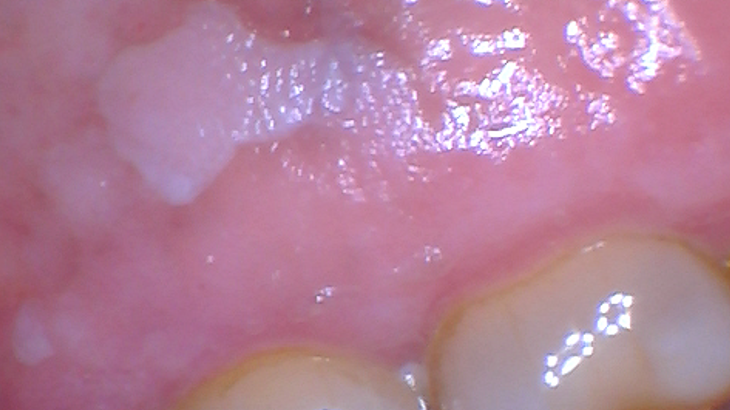

Leukoplakia specimens are often described by clinicians as being asymptomatic, white, red, or speckled (mixed), and they can have varying surface textures such as smooth, rough, pebbled, a thick keratin layer (hyperkeratosis), corrugated, or they may be fissured and may feature any of these combinations. These lesions are first diagnosed clinically through visual examination and palpation. Leukoplakia usually occurs in individuals over 40 years old, in less than 1% of the population with a 2%–3% annual risk of transformation. The worldwide prevalence is estimated at 1.5%–4.3%, but may be as high as 60% among the tobacco-smoking population.2,3

There have been studies documenting the usual etiology or suspects in what has been designated leukoplakia with tissue specimens submitted for biopsy confirmation. The lesions may also be histologically classified as homogeneous or nonhomogeneous.3 Some lesions are described as uniformly white with a thick surface that is flat or slightly wrinkled and homogeneous. Nonhomogeneous lesions may be white, red, ulcerated, or with a pebbly or verrucous surface. Additional categories used for these nonhomogeneous characteristics are: speckled leukoplakia (erythroleukoplakia), verrucous leukoplakia, and proliferative verrucous leukoplakia that has a high rate of progression to squamous cell carcinoma. The biopsy report of specimens submitted with a leukoplakia clinical diagnosis may be termed hyperkeratosis in approximately 80% of specimens as a pathology diagnosis. The remaining 20% will show some grade of dysplasia, cancer in situ, or invasive squamous cell carcinoma.3 These cellular changes are abnormal cells within tissue that are only identified through biopsy and microscopic evaluation. Precancerous-type lesions must be monitored when the initial cause cannot be determined.4 The suspected area may ultimately become malignant.